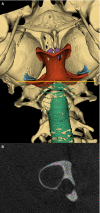

The synchronization of flight mechanics with respiration and echolocation call emission by bats, while economizing these behaviors, presumably puts compressive loads on the cartilaginous rings that hold open the respiratory tract. Previous work has shown that during postnatal development of Artibeus jamaicensis (Phyllostomidae), the onset of adult echolocation call emission rate coincides with calcification of the larynx, and the development of flight coincides with tracheal ring calcification. In the present study, I assessed the level of reinforcement of the respiratory system in 13 bat species representing six families that use stereotypical modes of echolocation (i.e. duty cycle % and intensity). Using computed tomography, the degree of mineralization or ossification of the tracheal rings, cricoid, thyroid and arytenoid cartilages were determined for non-echolocators, tongue clicking, low-duty cycle low-intensity, low-duty cycle high-intensity, and high-duty cycle high-intensity echolocating bats. While all bats had evidence of cervical tracheal ring mineralization, about half the species had evidence of thoracic tracheal ring calcification. Larger bats (Phyllostomus hastatus and Pterpodidae sp.) exhibited more extensive tracheal ring mineralization, suggesting an underlying cause independent of laryngeal echolocation. Within most of the laryngeally echolocating species, the degree of mineralization or ossification of the larynx was dependent on the mode of echolocation system used. Low-duty cycle low-intensity bats had extensively mineralized cricoids, and zero to very minor mineralization of the thyroids and arytenoids. Low-duty cycle high-intensity bats had extensively mineralized cricoids, and patches of thyroid and arytenoid mineralization. The high-duty cycle high-intensity rhinolophids and hipposiderid had extensively ossified cricoids, large patches of ossification on the thyroids, and heavily ossified arytenoids. The high-duty cycle high-intensity echolocator, Pteronotus parnellii, had mineralization patterns and laryngeal morphology very similar to the other low-duty cycle high-intensity mormoopid species, perhaps suggesting relatively recent evolution of high-duty cycle echolocation in P. parnellii compared with the Old World high-duty cycle echolocators (Rhinolophidae and Hipposideridae). All laryngeal echolocators exhibited mineralized or ossified lateral expansions of the cricoid for articulation with the inferior horn of the thyroid, these were most prominent in the high-duty cycle high-intensity rhinolophids and hipposiderid, and least prominent in the low-duty cycle low-intensity echolocators. The non-laryngeal echolocators had extensively ossified cricoid and thyroid cartilages, and no evidence of mineralization/ossification of the arytenoids or lateral expansions of the cricoid. While the non-echolocators had extensive ossification of the larynx, it was inconsistent with that seen in the laryngeal echolocators.